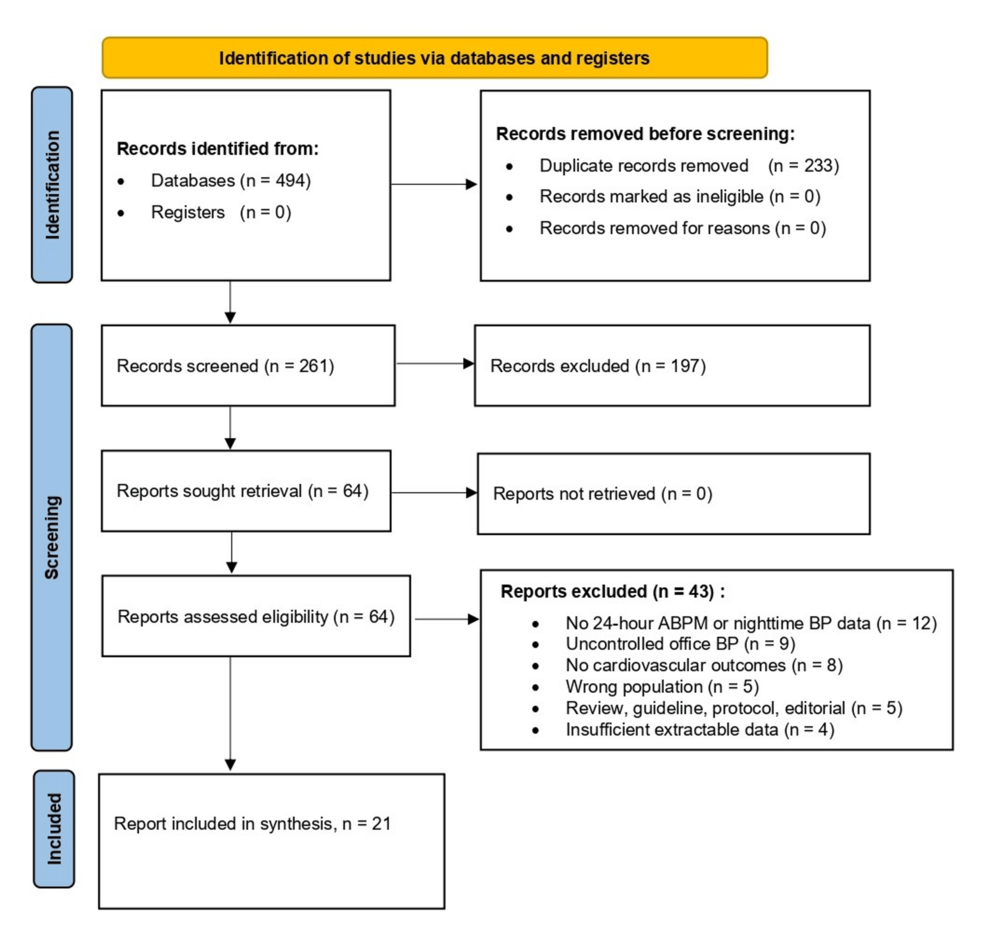

Masked Nocturnal Hypertension and Hidden Organ Risk: A Systematic Review (www.cureus.com)